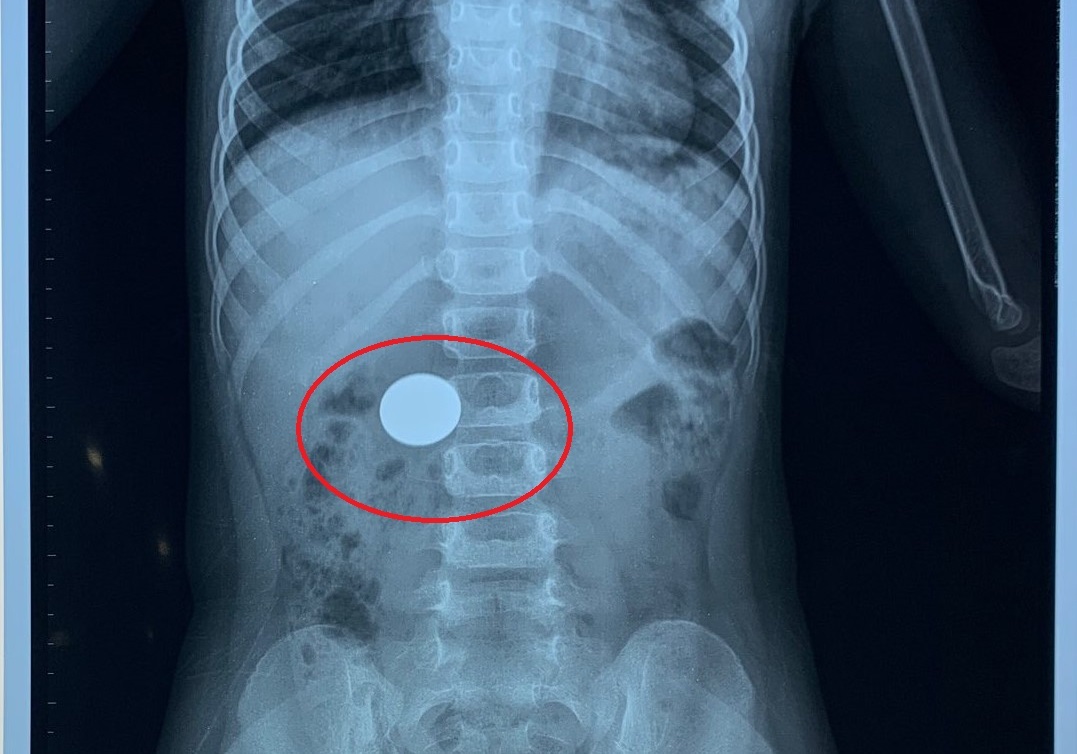

| Hình ảnh chụp Xquang cho thấy đồng xu trong dạ dày |

Lo lắng, chị M. đưa con đi khám thì phát hiện có đồng xu trong dạ dày bé N,.

Sau 30 phút, tiến hành nội soi can thiệp các bác sĩ gắp ra ngoài một đồng xu kim loại, đường kính 2 cm.